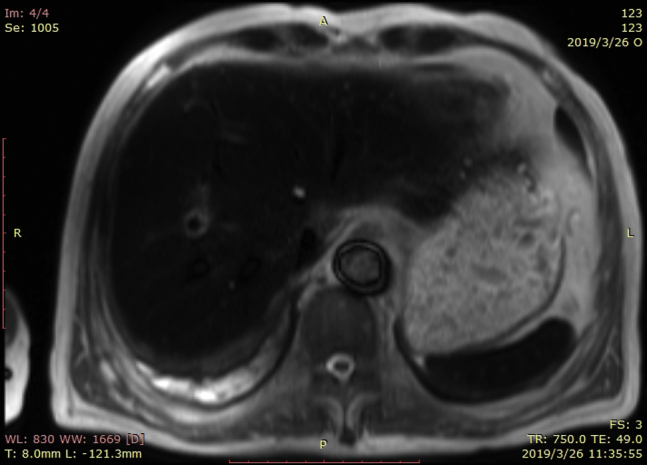

Upon the patient’s presentation to our hospital, blood test results showed an abnormal elevation in B-type natriuretic peptide levels, with a value of 1186 pg/mL (0–100 pg/mL). Compared with the patient’s ultrasound cardiography (UCG) 4 months prior, his recent UCG showed marked enlargement of the heart, with a left ventricular end-diastolic diameter of 61 mm, a right ventricular internal diameter of 43 mm, and reduced ejection fraction of 41% (Figure 1). The patient had extremely elevated levels of serum ferritin, with a value of 2497.80 ng/mL. Magnetic resonance imaging showed a significant decrease in signal intensity on T2-weighted images in the liver parenchyma (Figure 2). The ECG obtained on initial presentation revealed a J-point elevation of >2 mm, followed by T-wave inversion in the right precordial leads (V1 to V3) (Figure 3A). On the third day after admission, the patient started feeling severe dyspnea associated with intermittent palpitations. Urgent ECGs were performed and evaluated (Figure 3B), which showed frequent regular, wide QRS complex tachycardia with a rate of 100 beats per minute.

Figure 1.

Ultrasound cardiography (UCG) testing upon this presentation and about 4 months before this hospitalization. A: Apical 4-chamber view of UCG testing upon this presentation. B: Optimal parasternal long-axis view of UCG testing upon this presentation. C: Apical 4-chamber view of UCG testing about 4 months before this hospitalization. D: Optimal parasternal long-axis view of UCG testing about 4 months before this hospitalization.

The patient experienced progressive dyspnea with edema in both lower extremities. B-type natriuretic peptide levels were abnormally high and UCG showed that the whole heart was significantly enlarged, which confirmed that the patient had developed cardiomyopathy and congestive heart failure. Because this patient had received a large volume of RBCs to relieve his severe myelosuppression symptoms, he had extremely elevated levels of serum ferritin, with a value of 2497.80 ng/mL. Serum ferritin can reliably predict cardiac iron overload when levels are >2485 ng/mL.2 The manifestation of his abdominal magnetic resonance imaging, a significant decrease in signal intensity on T2-weighted images in the liver parenchyma, is consistent with iron overload. Cardiac iron deposition can result in cardiomyopathy, arrhythmia, and heart failure.3 We suspected that cardiac iron overload was the underlying cause of the patient’s ECG abnormalities and clinical manifestations. In addition, the management of heart failure and iron chelation therapy led to resolution of VT and Brugada pattern, which also supported our suspicions.